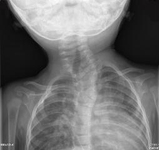

Congenital torticollis

Cervical spine x-ray showing numerous segmentation anomalies associated with a convex left cervicothoracic scoliosis. This patient presented with a head tilt. There are segmentation anomalies in the lower thoracic and high cervical region. There is an acute convex left cervicothoracic scoliosis with a hemivertebra at the apex of the curve. Butterfly vertebra is identified rostral to the hemivertebra, and segmentation anomalies are also identified caudal to the hemivertebra

From the personal collection of Dr Joyce L. Oleszek; used with permission